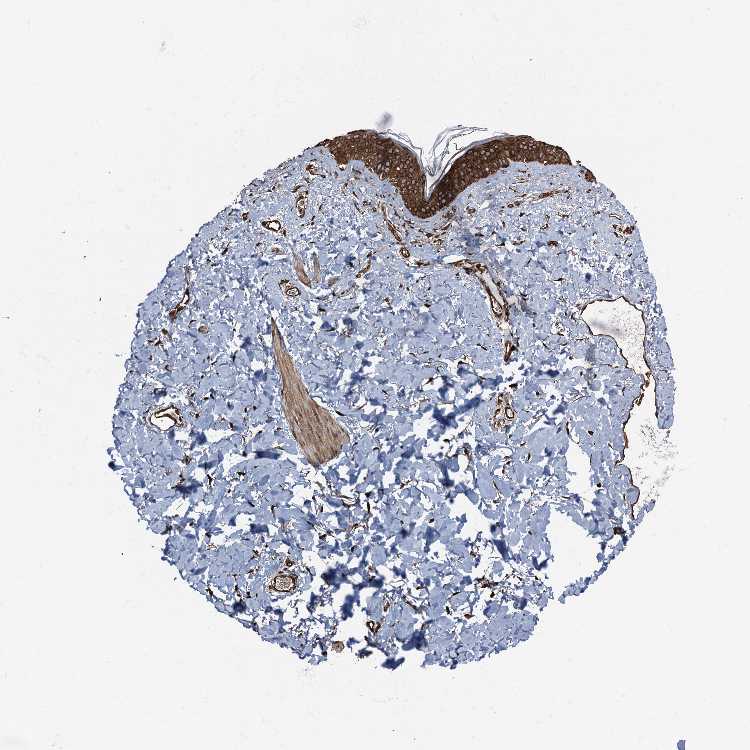

SKIN 2 - Antibody stainingi

Antibody staining in the annotated cell types in the current human tissue is reported as not detected, low, medium, or high, based on conventional immunohistochemistry profiling in selected tissues. This score is based on the combination of the staining intensity and fraction of stained cells.

Each image is clickable and will lead to virtual microscopy that enables deeper exploration of all samples and also displays staining intensity scores, fraction scores and subcellular localization as well as patient and tissue information for each sample.

Antibody HPA035116Antibody CAB010207

Cells in basal layer High-

Cells in corneal layer Not detected-

Cells in granular layer High-

Cells in spinous layer High-

Endothelial cells High-

Epidermal cells -Medium

Extracellular matrix Not detected-

Fibrohistiocytic cells High-

Langerhans cells High-

Lymphocytes High-

Melanocytes High-

Vascular mural cells High-